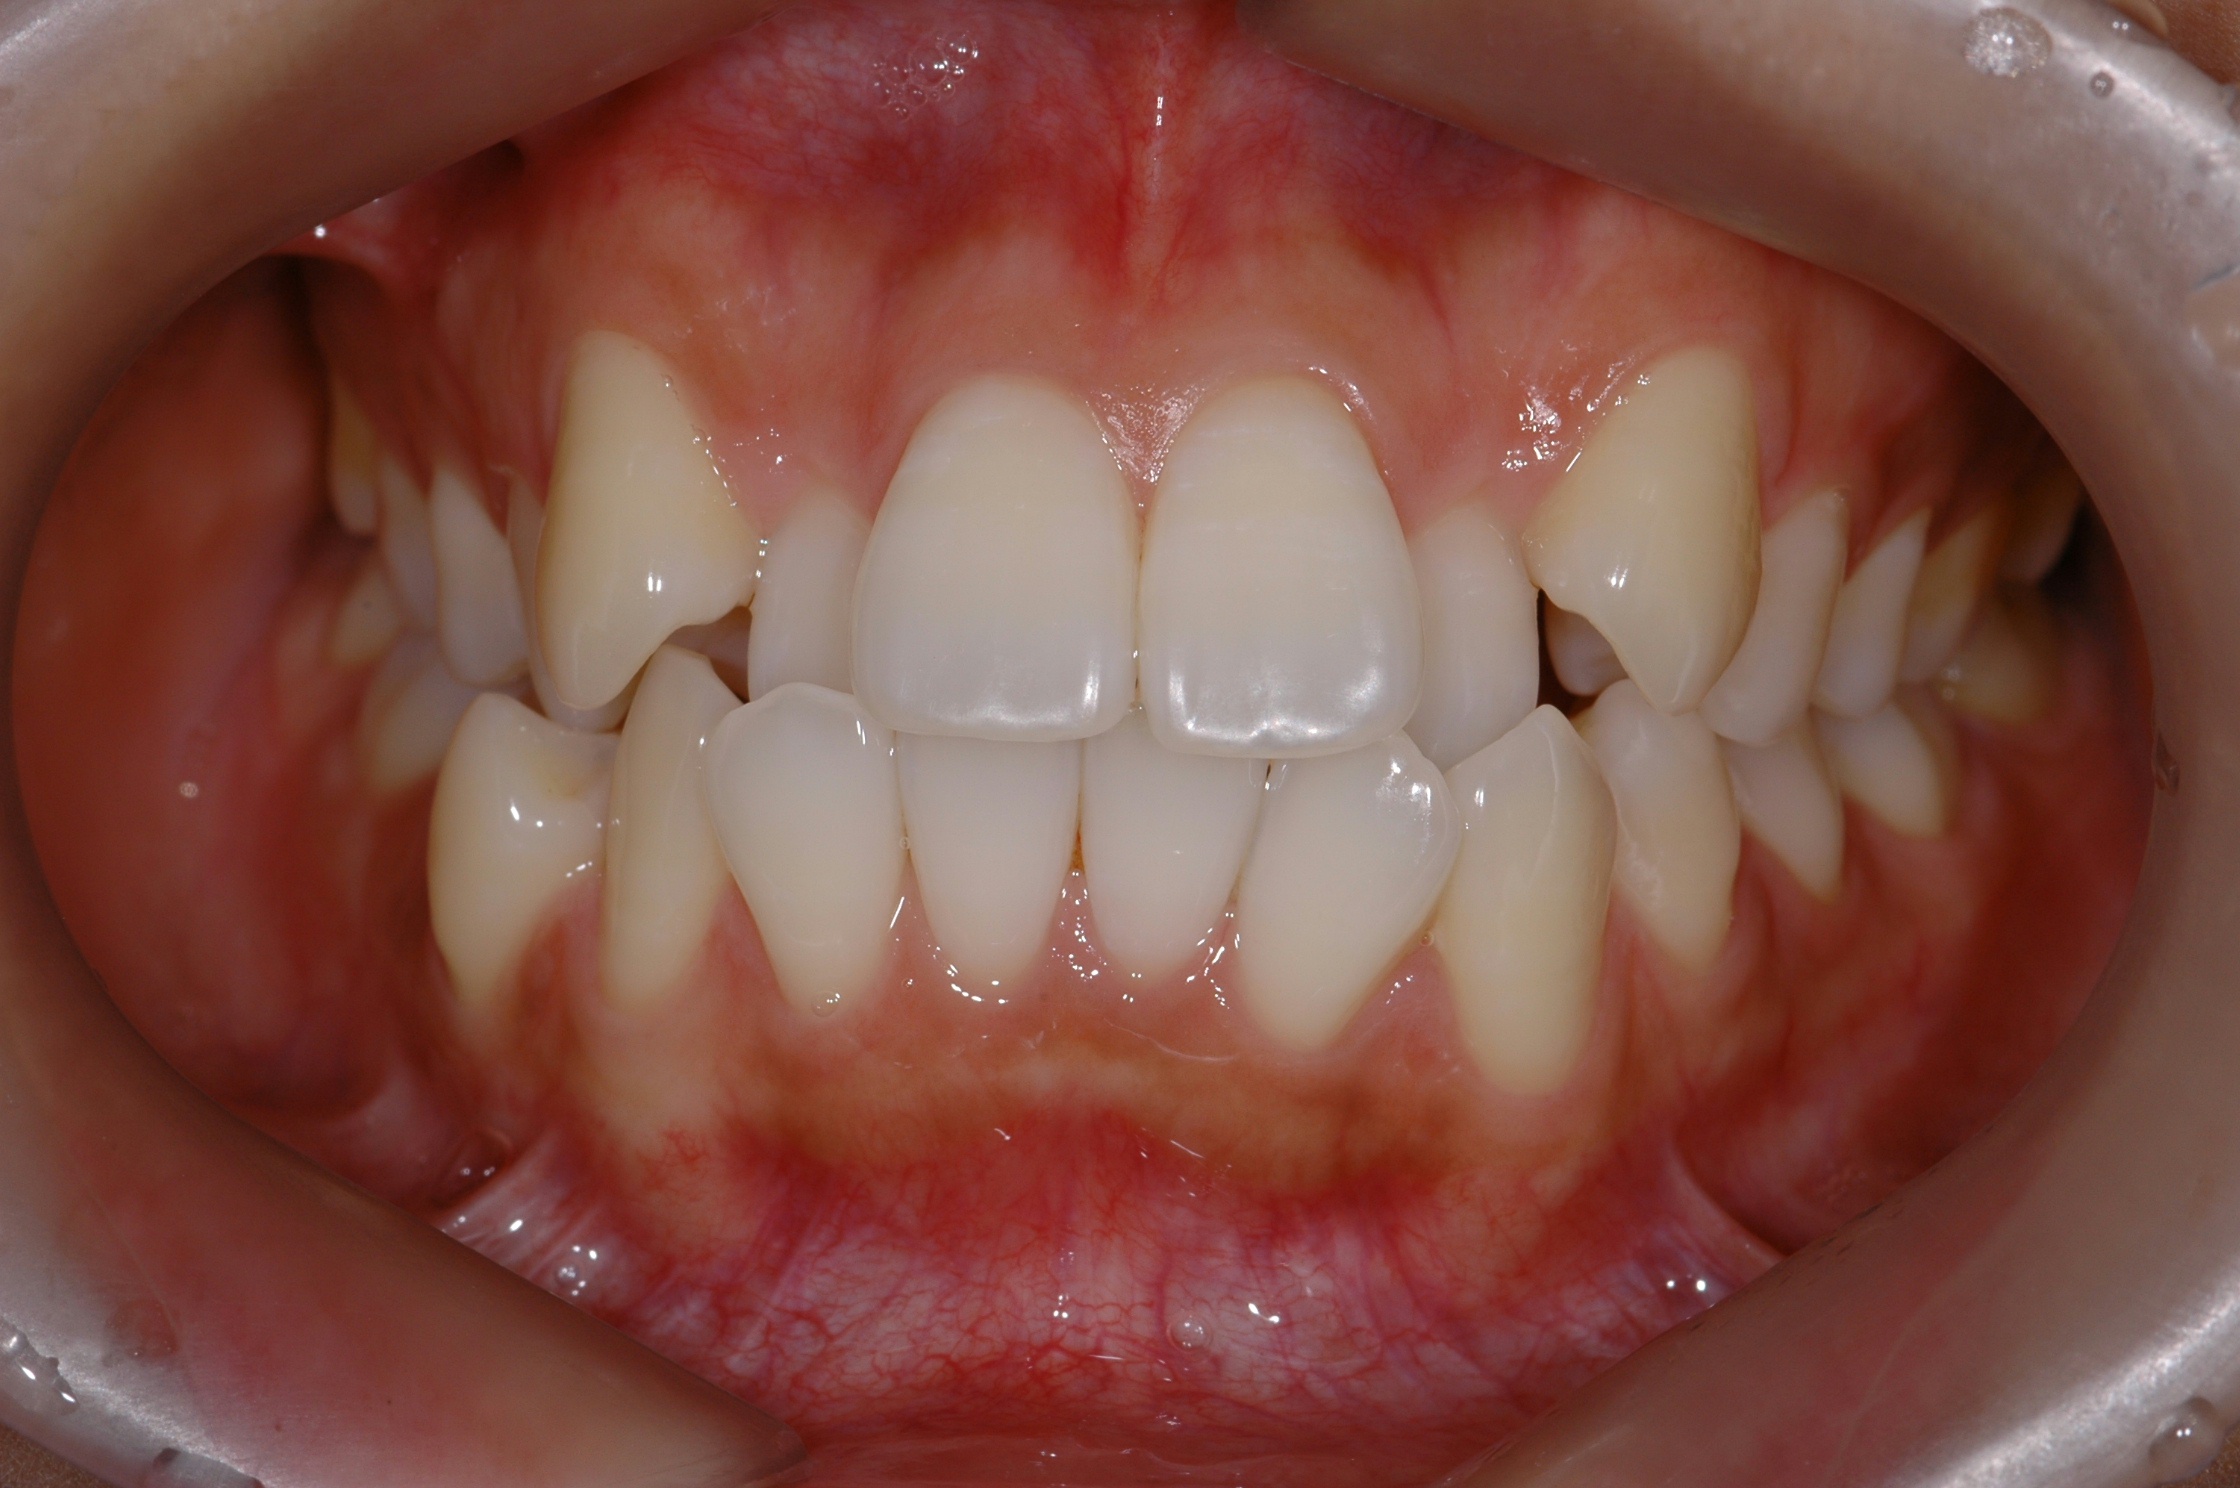

치료 전 사진입니다.